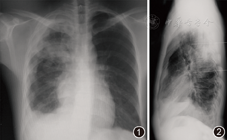

患者男,24岁,无业。3个月前因受凉后出现咳嗽,咳少量白色黏痰,伴发热,最高体温38.5 ℃,热型不详,无畏寒、盗汗、咯血和胸痛,右下胸壁出现一无痛柔软包块,在当地医院使用青霉素等抗感染治疗,1周后体温正常,仍有间断咳嗽,咳少量黄色黏稠痰,胸壁包块逐渐增大。在广州市某肿瘤医院就诊,胸部CT示胸膜多发囊性病变,右胸壁肿物穿刺涂片可见坏死及炎症细胞,未见癌细胞。患者于2007年10月11日在广州医学院第一附属医院呼吸疾病研究所就诊,以胸膜多发囊性病变待查入院。患者既往从事车床加工1年余,吸烟史4年,每日约5支,曾有生食芫荽菜史,无其他病史,发病以来体重减轻约2 kg。体检:体温36.7 ℃,呼吸22次/min,血压108/66 mm Hg(1 mm Hg=0.133 kPa),皮肤黏膜未见异常;双腋下可触及多个淋巴结,直径约为1.5 cm,光滑、无压痛、活动度好;右前下胸壁可见一直径约为3.5 cm的类椭圆形肿块,大小随呼吸运动无明显改变,无压痛,皮下无滑动感;剑突处右侧腹壁可见一直径约为1.5 cm肿块,性状与前述肿物相似;右肺呼吸音稍减弱,双肺未闻及干湿啰音。其他系统未见异常。血常规检查:白细胞数为14.4×109/L,中性粒细胞为0.85,淋巴细胞为0.08,嗜酸粒细胞为0.01,血红蛋白为116 g/L,血小板为5.3×109/L;尿、粪常规未见异常,ESR未查,血清MTB抗体阳性,裂头蚴抗体弱阳性,包虫、囊虫、肺吸虫、肝吸虫和血吸虫等寄生虫抗体均为阴性,乙型肝炎表面抗体阳性,丙型肝炎抗体、人免疫缺陷病毒抗体和梅毒血清学试验均为阴性,肿瘤标志物:神经元特异性烯醇化酶为18.9 mg/L,非小细胞肺癌相关抗原、癌胚抗原、CA125抗原和CA153抗原均未见异常,抗链球菌溶血素O试验为613 U,C反应蛋白为4.4 mg/L,类风湿因子为10 kU/L,IgA为19.8 g/L,IgG为7.4 g/L,IgM及补体C3、C4和CH50均在正常范围,抗中性白细胞胞质抗体(胞质型和核周型)和抗核抗体均为阴性,血管紧张素转化酶为17.3 μmol·min–1·L–1,嗜酸粒细胞阳离子蛋白为45.4 μg/L,D–二聚体为495 mg;X线胸片示右上肺后段有斑片状渗出,右侧胸膜呈弥漫性连贯波浪状增厚,边缘光滑,密度均匀,右侧膈面升高,右侧肋膈角变钝(图1,图2)。考虑为右上肺渗出性肺结核,左上肺增殖性肺结核,右侧广泛胸膜结核。

外院胸部CT会诊考虑为右上肺浸润型肺结核,右侧胸膜和胸壁及右锁骨上窝转移性多发坏死性结核病变(图3,图4,图5,图6,图7,图8)。B超检查示:右上腹低回声团块,与右膈上相连通,结合临床表现考虑为结核性病变,剑突下及右胸壁肋骨后方多发实性占位病变,血流不丰富;右膈下实性占位性病变;肝、胆、脾、胰等脏器未见异常;左肾下盏有3 mm×3 mm强光团,回声不明显,不除外结石;右肾和膀胱未见异常。肺功能检查提示中度限制性通气功能障碍,肺总量减少,残气容积增高,残气容积/肺总量升高,弥散功能中度下降。临床诊断为右上肺结核、右侧胸膜结核和右胸腹壁结核。右侧胸壁肿物采用潜行穿刺术抽取脓液涂片找抗酸杆菌阴性,PCR法检查MTB–DNA为阳性。经手术摘除右胸壁肿物,为3.5 cm×3 cm不规则组织,表面灰红和暗红色,质地粗糙,一侧为1个囊腔,囊内壁灰红色,质地粗糙。抽取其中脓液涂片查找抗酸杆菌(++),未发现真菌和阿米巴原虫等,PCR法检查MTB–DNA阳性,抗酸杆菌培养阳性,涂片未找到癌细胞;镜下可见胶原纤维增生、多个结核样结节及结核性肉芽肿,肉芽组织内血管丰富,部分区域可见干酪样坏死(图9),抗酸、阿辛蓝、六胺银染色和过碘酸希夫反应均为阴性。最终诊断为右上肺继发性肺结核,右侧广泛胸膜结核和右胸腹壁结核。遂转入广州市胸科医院治疗。经电话随访,患者采用正规抗结核治疗1年后痊愈停药,每年在当地医院复查X线胸片,肺结核无复发,未再复查CT。

本例患者的X线胸片和胸部CT扫描均显示右上肺后段有斑片状渗出,这是典型继发性肺结核的影像学表现。病变同侧胸膜多发弥漫性囊性病变,同一层面具有2层以上囊腔,增强CT扫描示所有囊壁均有完整强化,同侧胸腹壁可见多个囊性病变,经病理学和病原学检查证实为结核病。胸膜多发囊性病变可能为多发胸膜结核病灶,每个病灶均有结核性肉芽肿形成,中央干酪样坏死液化形成脓肿。增强CT扫描时,因肉芽组织内供血丰富而表现为环形强化。胸膜腔囊性病变还可见于胸膜异位胰腺组织伴假性囊肿形成、心包胸膜囊肿、肺吸虫病、囊性畸胎瘤等,上述疾病多为单发囊性病变。而皮样囊肿、良性多房囊性胸膜间皮瘤、包虫病等可出现胸膜腔多发囊性病变,但极为少见。上述各种胸腔囊性病变其影像学表现无明显特征性,应注意鉴别,一般需通过病理或病原学检查确诊。